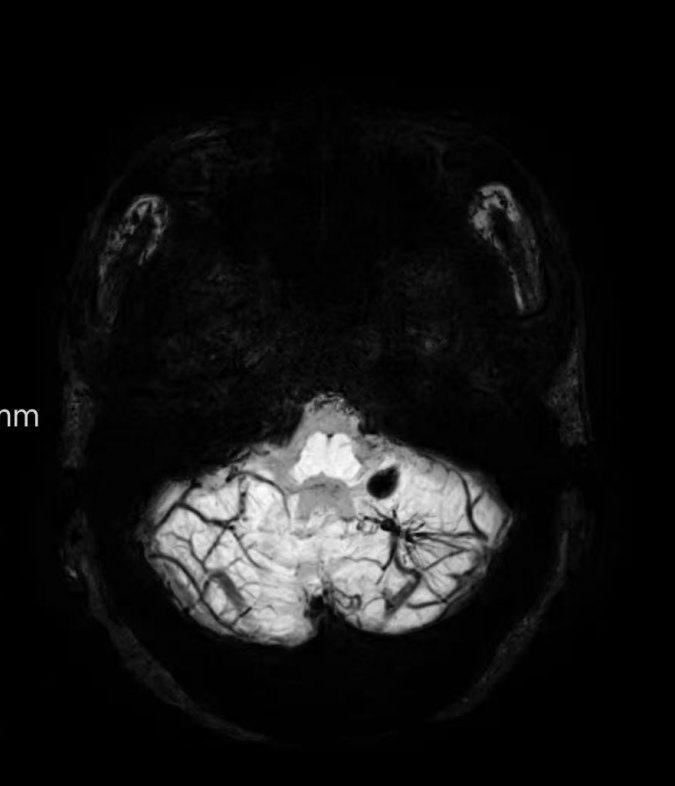

臨床中遇到一位患者,中年女性,反復出現(xiàn)頭痛,時輕時重,常規(guī)CT及磁共振檢查無明顯異常發(fā)現(xiàn),最后建議加做一個磁共振磁敏感加權成像(SWI),結果發(fā)現(xiàn)是左側(cè)小腦發(fā)育性靜脈畸形(DVA),SWI清晰顯示畸形的靜脈及周圍含鐵血黃素沉積;如下圖。這正是她頭痛的原因。

①診斷靜脈畸形:SWI能高精度地顯示發(fā)育性靜脈畸形——一種常見的腦血管畸形。在SWI上,發(fā)育性靜脈畸形會呈現(xiàn)典型的“海蛇頭”或“水母頭”征,即一堆細小的髓靜脈匯入一支粗大的引流靜脈。